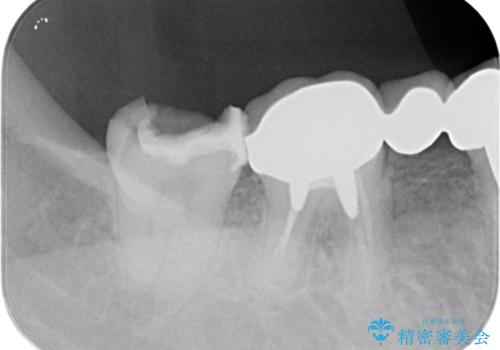

インレー下に再発した虫歯 セラミッククラウンによるやり替え

- 「食事の際にバキッと音がした。心配なので見てほしい。」と歯の検診を希望され来院されました。

視診にて、インレーの破折、インレー下に虫歯が再発していることを認めました。

壊れてしまったインレーおよび、虫歯を神経を温存できるよう丁寧に除去したのち、耐破折に優れるセラミッククラウンで再補綴治療を行います。